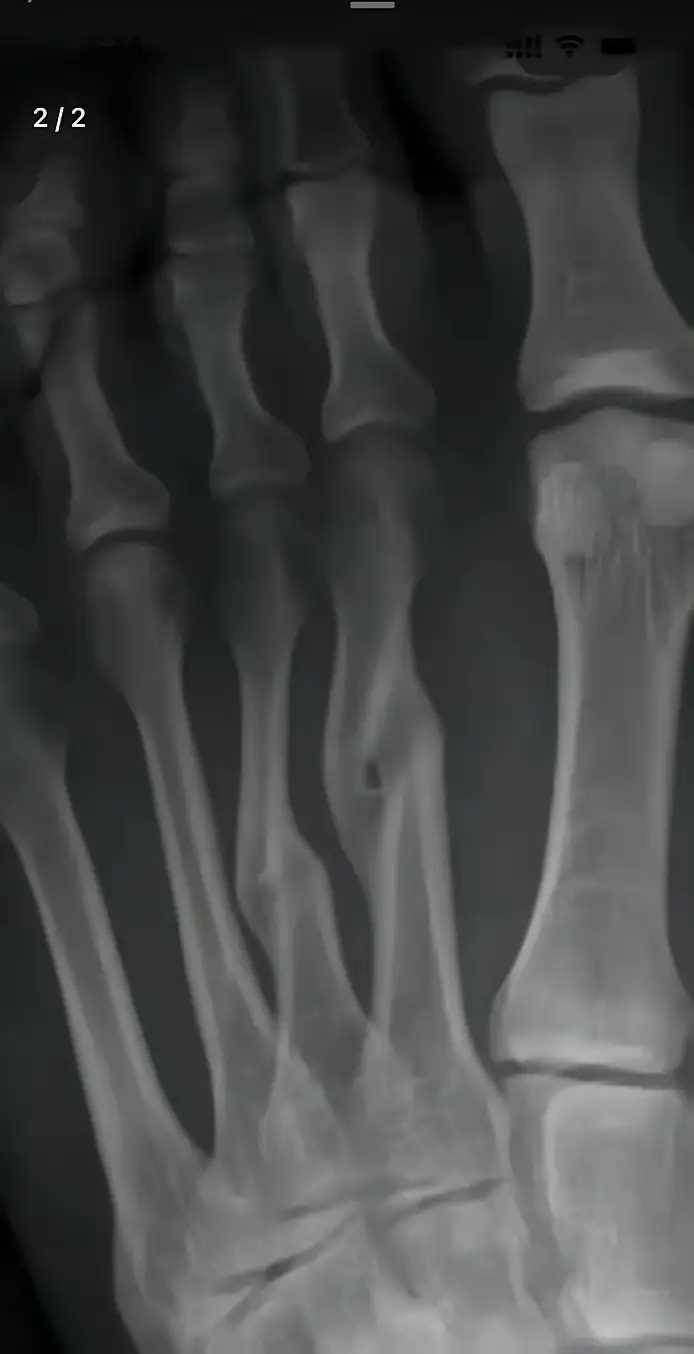

那張X光片靜靜躺在醫生手中,清晰顯示著第三蹠骨的斷裂與錯位——這是李阿嬤三個月前拒絕手術時留下的影像。當時,家人們圍在病床邊心急如焚:「媽,這骨頭都錯位了,不開刀會落下終身殘障的!」

三個月裡,兒女們每日提心吊膽。看著母親腫脹未消的腳踝,看著那明顯凸起的部位,他們已做好照顧殘障老人的準備。直到復查那天,新的X光片讓所有人都愣住了——原本錯位的斷骨,竟在未手術的情況下,奇跡般地長合在一起了。

「這……」醫生推了推眼鏡,仔細比對著新舊兩張片子,「雖然癒合處有輕微隆起,關節面也略顯不平,但確實自然癒合了。」他指著片子解釋:「人體骨骼本身就有強大的自愈能力,手術的鋼釘鋼板只是幫助復位,真正讓骨頭連線的,還是身體自身的成骨細胞。」